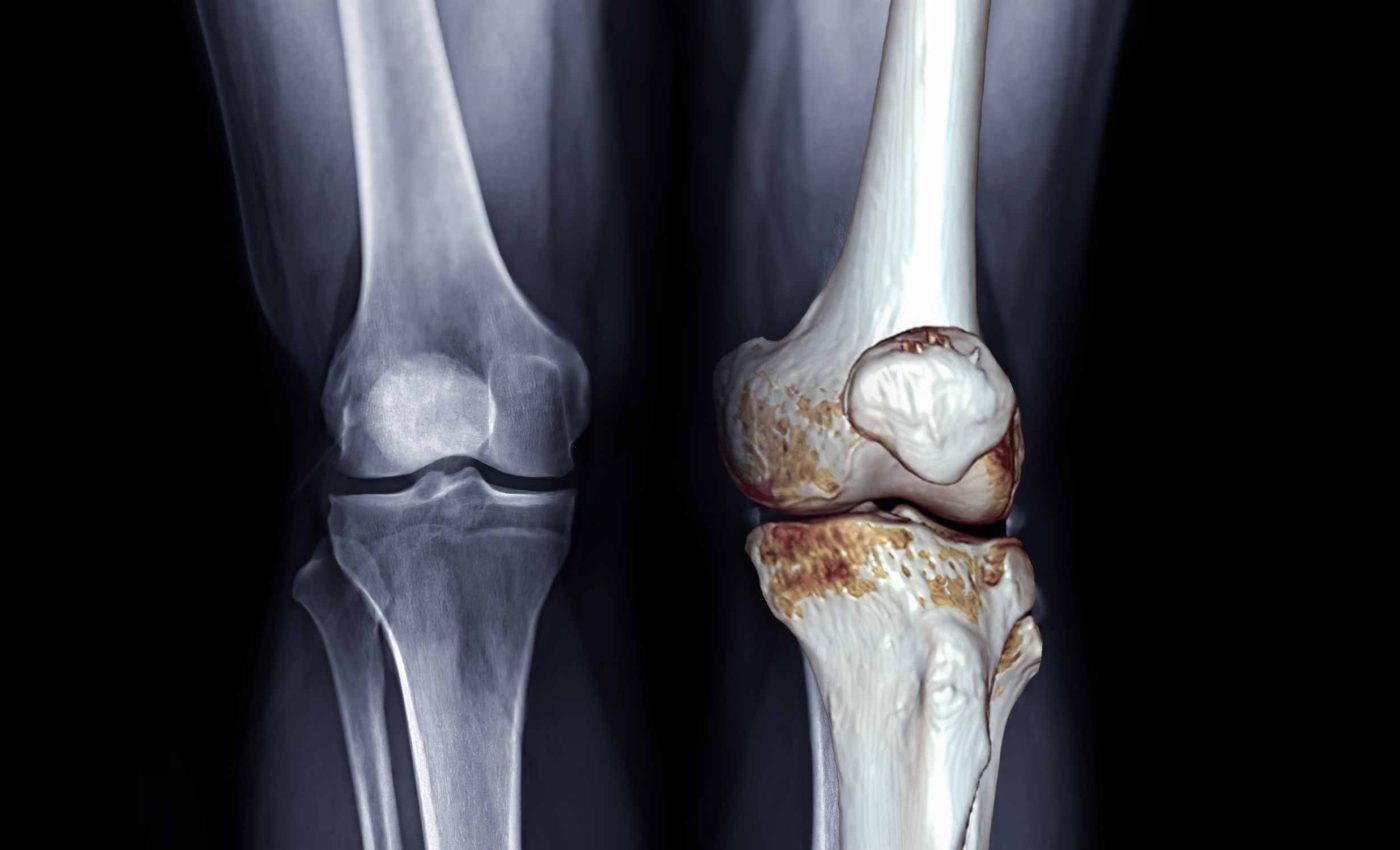

Most people with osteoarthritis, a joint disease that slowly damages cartilage and limits movement, are told to manage pain with pills.

A knee brace for arthritis is usually a rigid or semi rigid device that wraps around the joint. By changing how body weight passes through the knee, the brace can take pressure off the worn compartment and reduce irritation of sensitive tissues.

Clinical research on unloader braces, rigid supports that relieve pressure from one side of the knee, shows clear short term pain relief. Several trials also report better function and longer walking distance when people use these braces consistently.